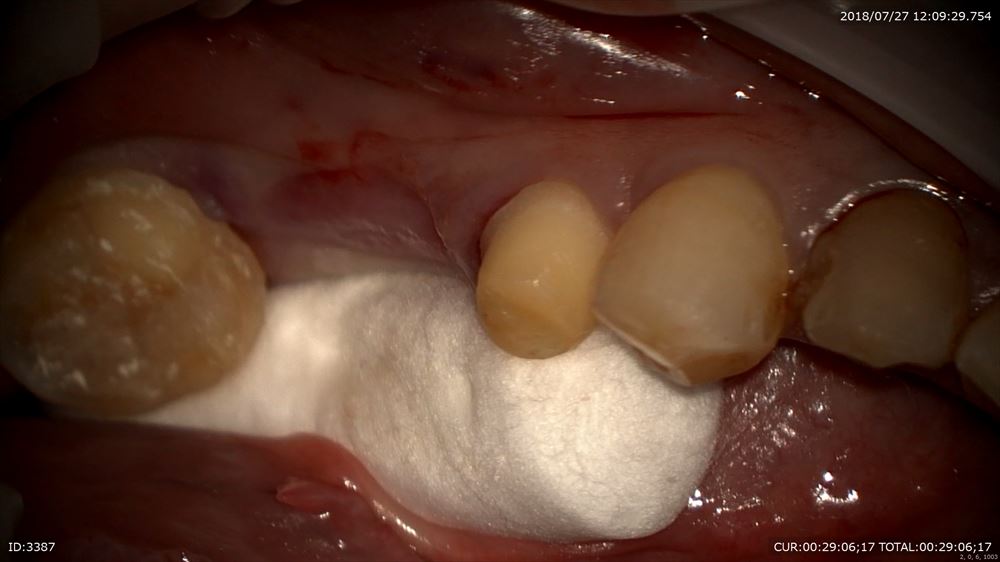

仮歯を外してセット

かみ合わせ調整

隙間0の被せ物。

歯がない部分も押してモディファイドオべイド。

このような仕事を100%当院では行います。保険だからとか自費だから、時間がないからとか院長の機嫌がとかではなく